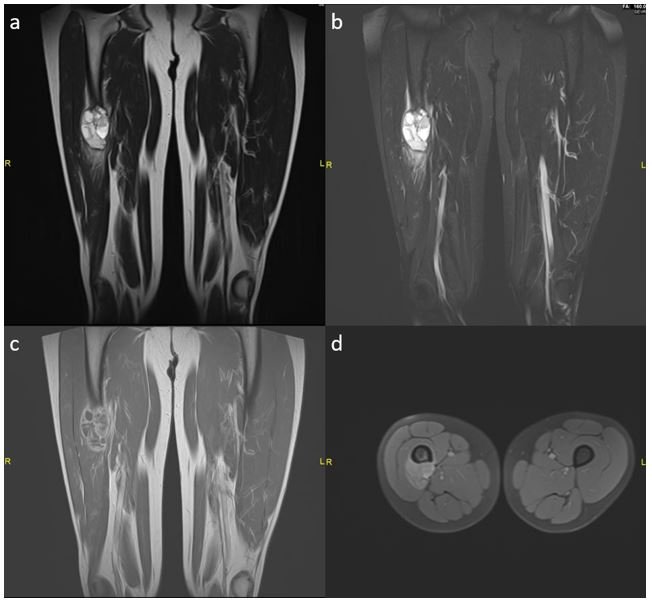

Figure 2: MRI features of lesion: multi-locular cystic lesion with peri-tumoral soft tissue edema in T2 and T2 STIR (Figure 2a and 2b); post-contrast peripheral enhancement with periosteal location in T1 gad+ (Figure 2c) and T1 FS gad+ (Figure 2d).